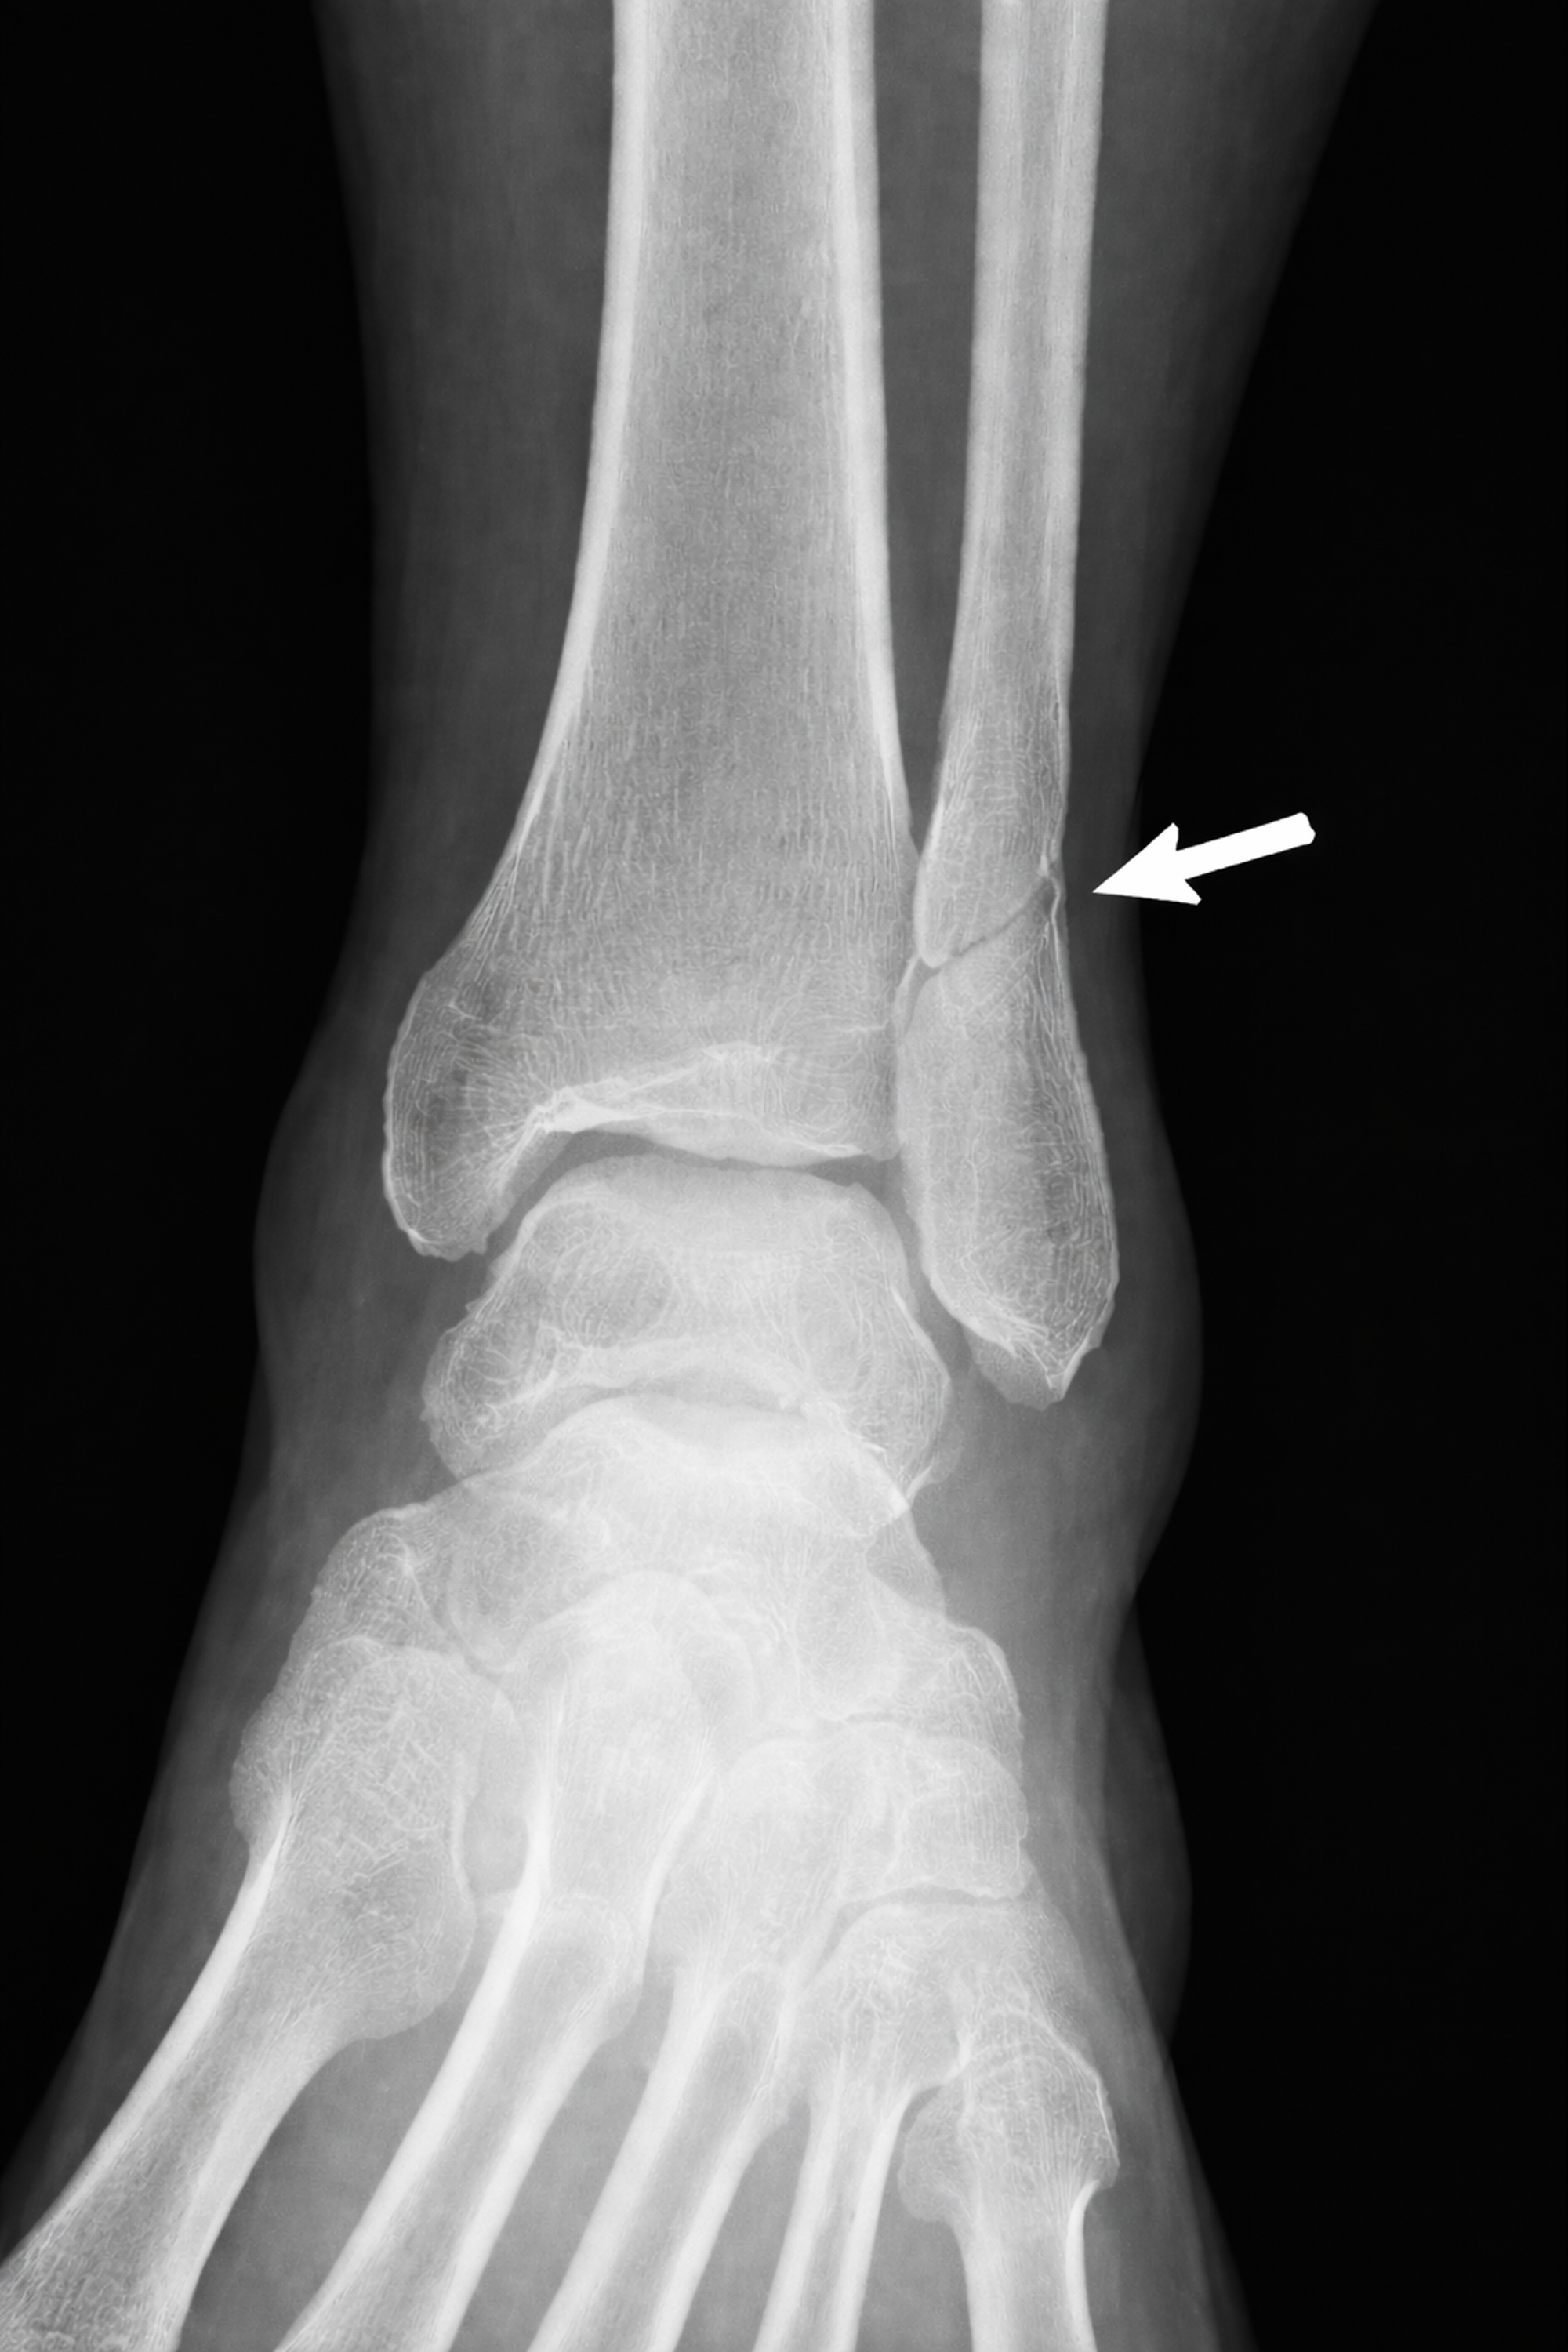

Figuur 2

Een Weber B-fractuur komt vaak voor. Het is een breuk van het kuitbeen ter hoogte van de enkelbandverbinding (syndesmose). Uit de röntgenfoto’s blijkt dat het bij u om een stabiele Weber B-fractuur gaat. Dit betekent dat u 1 tot 2 weken gips zult krijgen, waarbij het belangrijk is dat u niet loopt. Na deze periode krijgt u een enkelbrace en kunt u, afhankelijk van de klachten, geleidelijk gaan belasten voor een periode van 4 tot 5 weken. Zes weken na de breuk komt u terug voor een controle op de gipskamer.

Een breuk in het kuitbeen komt vaak voor. Uit de extra röntgenfoto's blijkt dat u een stabiele breuk heeft. U krijgt 1 tot 2 weken een gipsverband, waarmee u niet mag lopen. Daarna krijgt u een enkelbrace, zodat u rustig kunt beginnen met belasten.